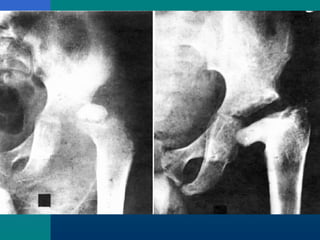

TB HIP- X-RAYTB HIP- X-RAY

 Osteoporosis

 Travelling acetabulum

 Dislocated hip

 Mortar and pestle appearance

 Perthes type

 Protrusio acetabuli

 Destruction of head